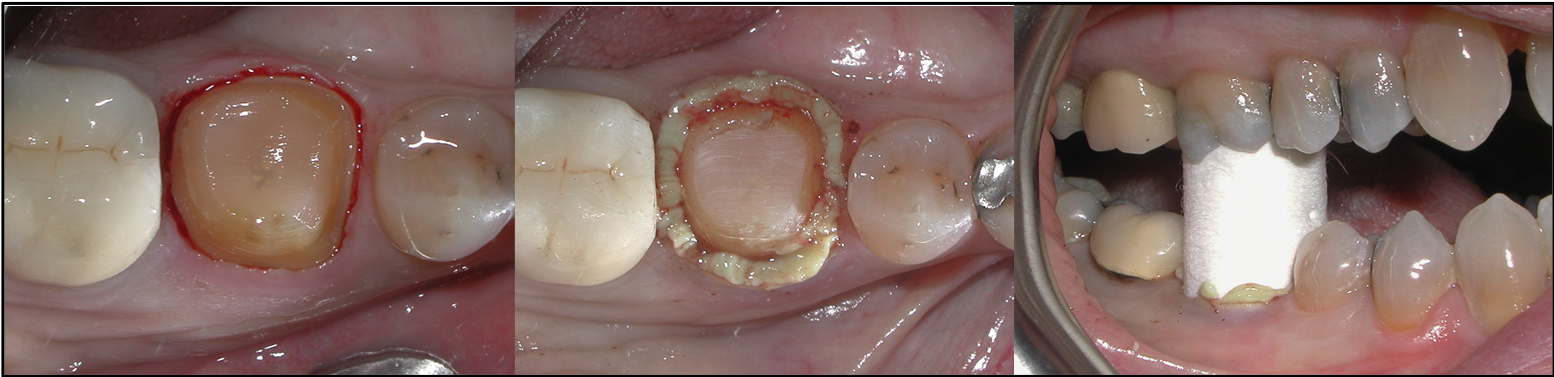

Fig 2. Different restorations and substrates require different preparation measurements.

Figure 2

Tooth preparation should be performed as dictated by the type and substrate of the final restoration. Various types of restorations and substrates require different preparation methods. For example, lithium disilicate, porcelain-fused-to-metal (PFM), and porcelain-fused-to-zirconia (PFZ) anterior crown preparations require 1.5 to 2.0 mm incisally, 1.5 mm facially and lingually, and 1.0 mm at the cervical third facially and lingually. Full zirconia crowns in the posterior require 1.0 mm at the cusp tips, 1.5 mm occlusally, 1.0 mm buccally and lingually, and .75 mm at the marginal areas (gingival third of the tooth). Lithium disilicate, PFM, and PFZ posterior crowns require 1.5 to 2.0 mm occlusally, 1.5 mm buccally and lingually, and 1.0 mm at the gingival third or at the margin area (Figure 2).